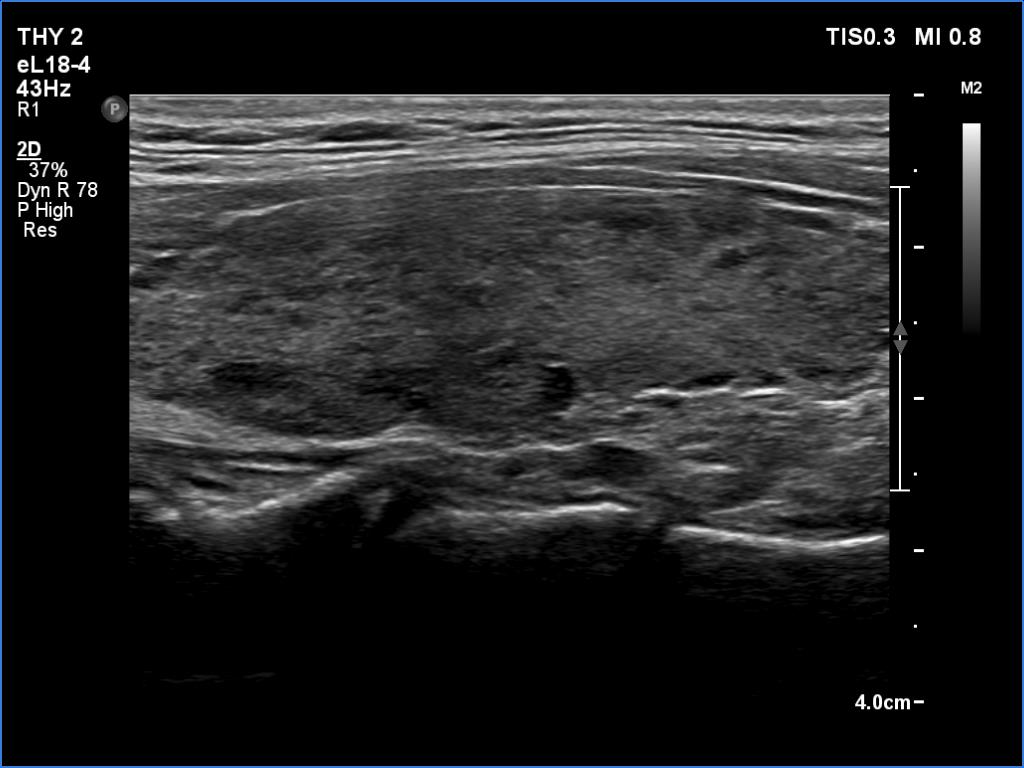

Left lobe, transverse scan